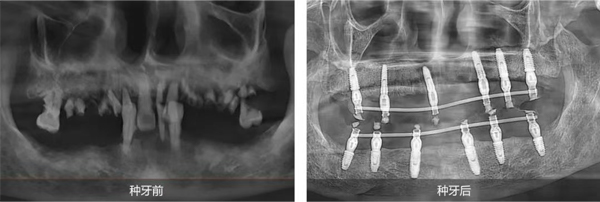

姜辰主任医疗团队为陈叔叔定制了全口即刻种植修复方案。该方案既能满足陈叔叔尽快恢复咀嚼功能的需求,又最大程度地减轻了他的痛苦,缩短了治疗周期。手术在陈叔叔家人的陪伴下顺利结束,当天,陈叔叔就戴上了临时牙冠,恢复了基础饮食功能。